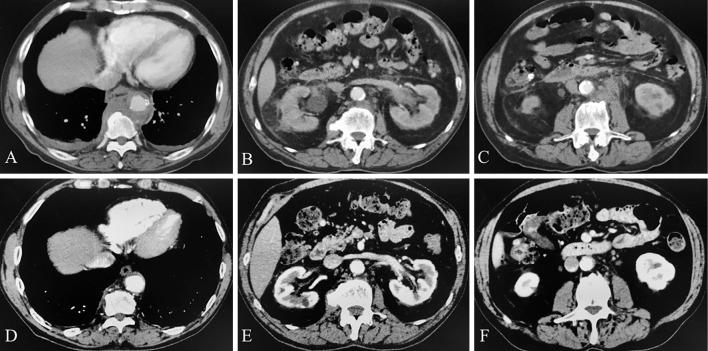

Some forms of idiopathic retroperitoneal fibrosis (RF) have recently been considered to be a part of the spectrum of immunoglobulin G4 (IgG4)-related disease. This case report is the first description of a spontaneous remission in a patient with pathologically proven IgG4-related RF. Although the pathogenesis and long-term disease behavior of IgG4-related RF remains unknown, we believe that an initial assessment consisting of only careful monitoring might be one important strategy, especially in asymptomatic IgG4-related RF patients without nephropathy, while carefully monitoring these patients for the risk of recurrence.

某些形式的特发性腹膜后纤维化(RF)最近被认为是免疫球蛋白G4(IgG4)相关疾病谱的一部分。本病例报告首次描述了一例经病理证实的IgG4相关RF患者的自发缓解情况。尽管IgG4相关RF的发病机制和疾病长期行为尚不清楚,但我们认为,仅由仔细监测组成的初始评估可能是一种重要策略,尤其是对于没有肾病的无症状IgG4相关RF患者,同时要仔细监测这些患者的复发风险。